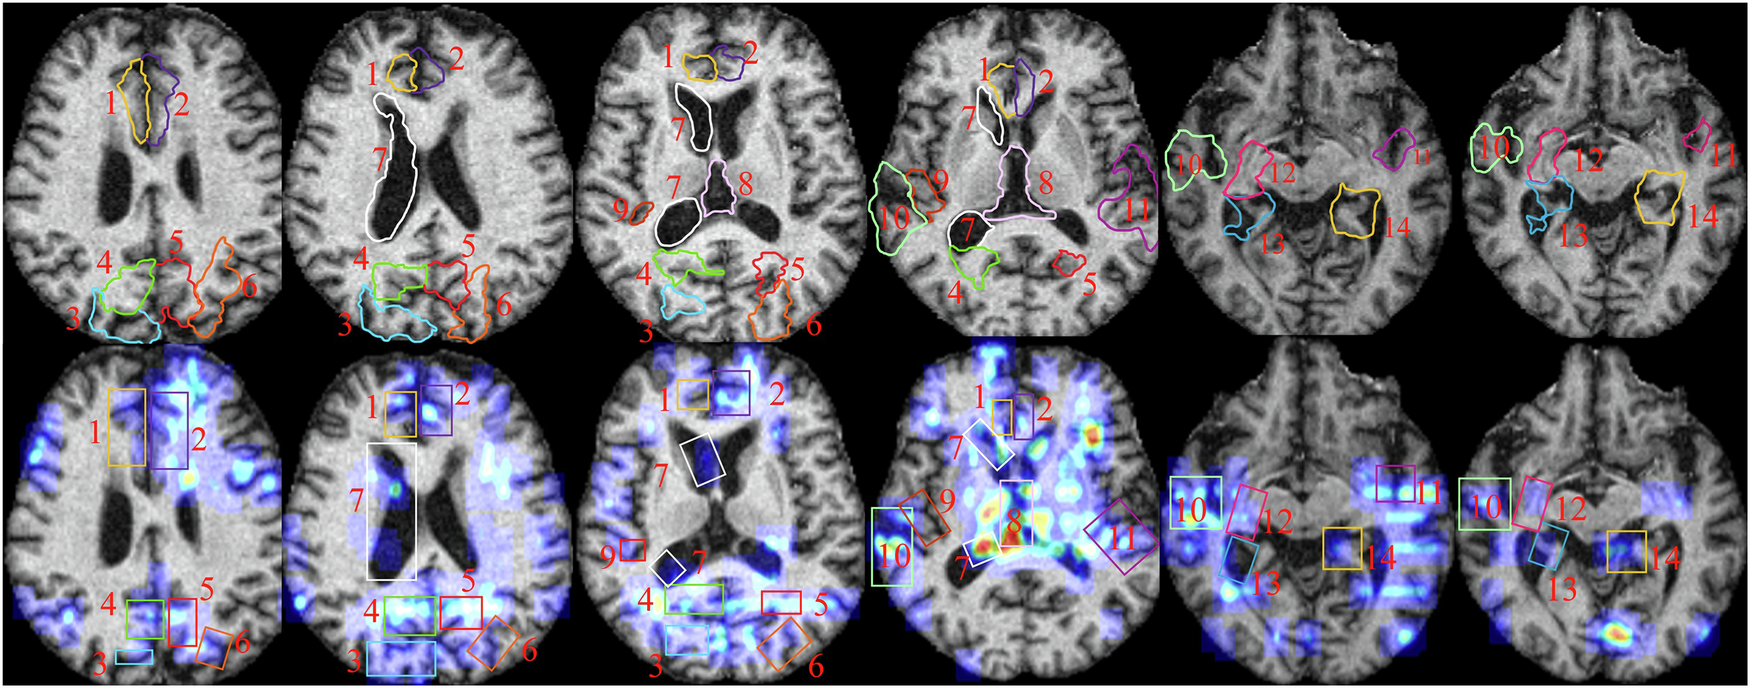

Fig. 4

From: A lightweight CVTC model for accurate Alzheimer’s MRI analysis and lesion annotation

Presents a comparative example of manual annotations by clinicians and automatic annotations generated by CAGM, highlighting key brain anatomical structures (regions of atrophy or abnormal enlargement) as follows: 1 is R. cingulate gyrus, 2 is L. cingulate gyrus, 3 is R. superior parietal gyrus, 4 is R. pre-cuneus, 5 is L. pre-cuneus, 6 is L. cingulate gyrus, 7 is R. lateral ventricle, 8 is third ventricle, 9 is R. transverse temporal, 10 is R. superior temporal gyrus, 11 is L. superior temporal gyrus, 12 is Bilateral Hippocampus, 13 is R. parahippocampal gyrus, and 14 is L. parahippocampal gyrus. This comparison enables a visual evaluation of the consistency and potential discrepancies in CAGM annotations across cortical and subcortical structures, serving as a reference for subsequent quantitative analysis.